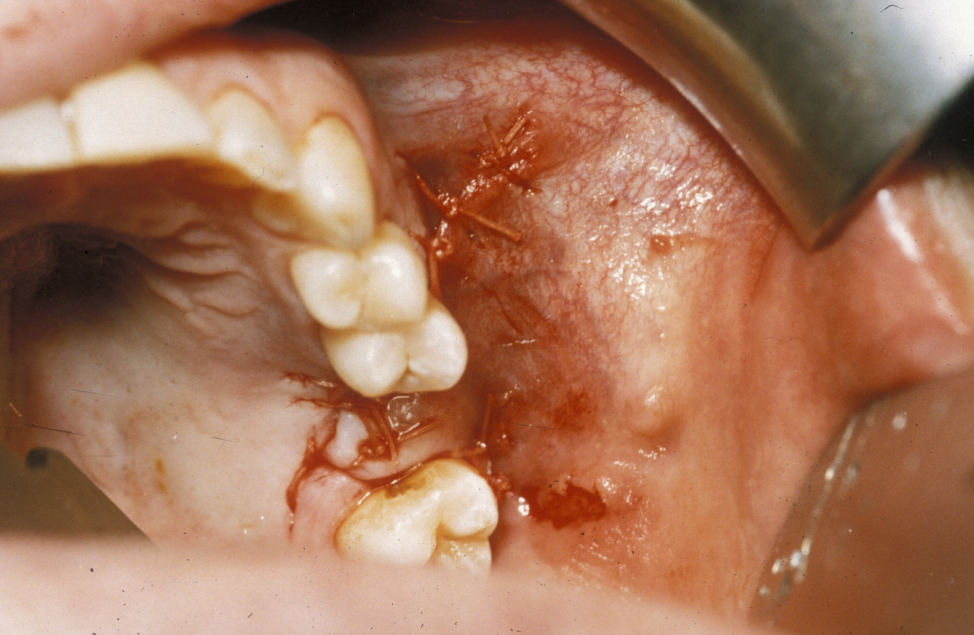

This procedure uses a three-sided advancement flap of buccal mucosa. The flap is mobilised by making an incision through the periosteum to allow the flap to be stretched without tension over the defect (Figure 1).

Figure 1: A buccal advancement flap is raised and mobilised by incising the periosteum. This also allows access to the buccal pad of fat (see below).

It is essential that the suture line rests on sound bone; otherwise this flap will inevitably dehisce (split). The disadvantages of the buccal advancement flap are a relatively shallow sulcus (groove between the jaw and the cheek) postoperatively and the risk of flap dehiscence because it is a single-layer closure and must be closed over bone (Figure 2).

Figure 2: Simple buccal advancement flap closure.